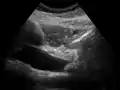

On abdominal ultrasonography, the common bile duct is most readily seen in the porta hepatis (where the CBD lies anterior to the portal vein and hepatic artery). The absence of Doppler signal distinguishes it from the portal vein and hepatic artery.